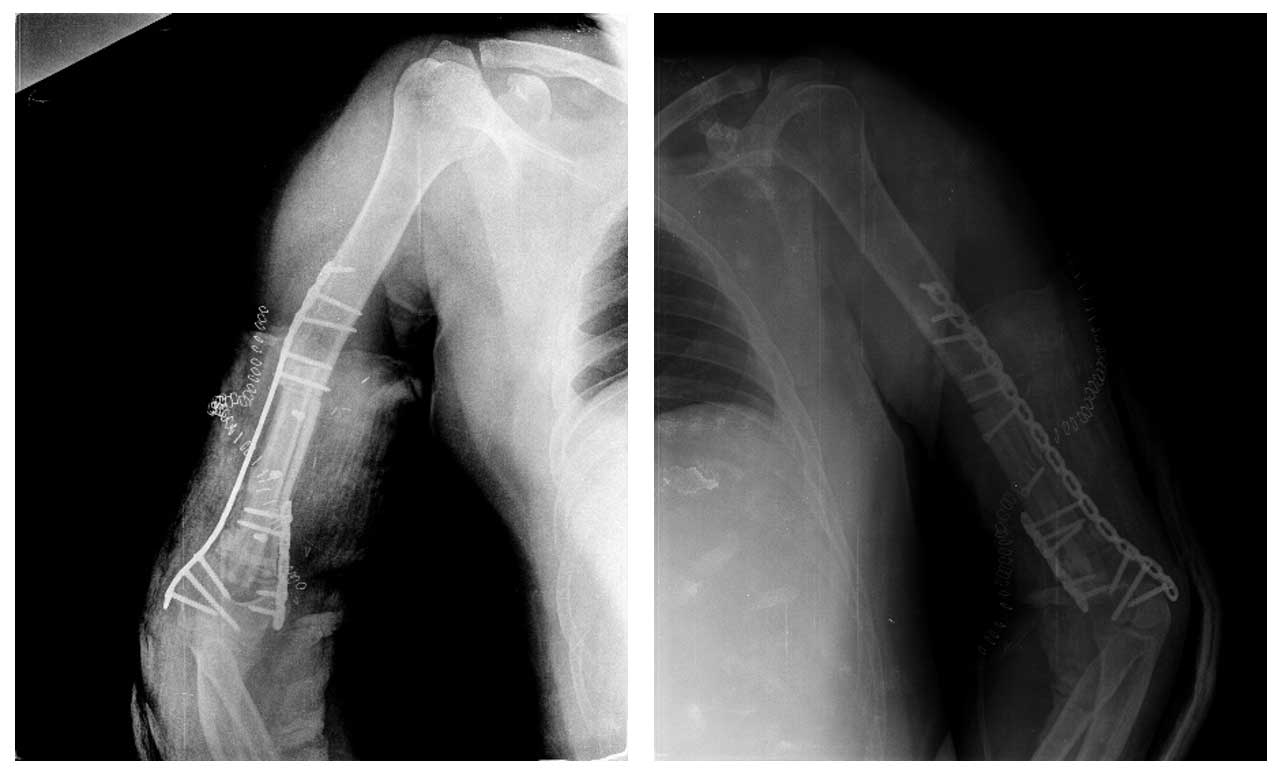

Ameliyat Sonrası: Röntgende geri kazanılan kemiğin çift plak ile fiksasyonu görülmekte.